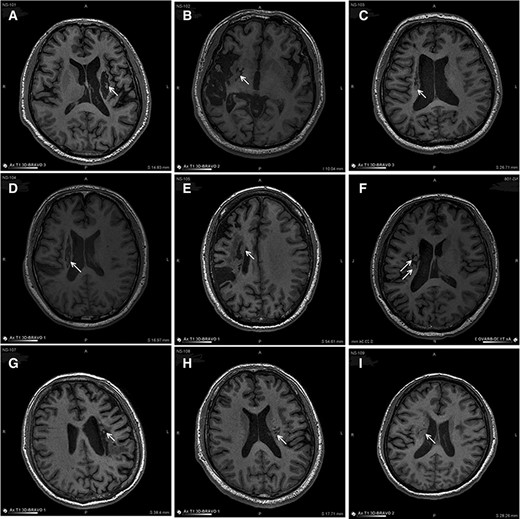

圖3:NSI-566移植后最新隨訪時(shí)梗塞部位的MRI。

圖中顯示的是所有9名受試者(#101–109)在NSI-566移植后最新隨訪時(shí)的T1MRI圖像。箭頭指示梗塞腔位置。

(A):#101,24個(gè)月時(shí),(B)#102,12個(gè)月時(shí),(C)#103,14個(gè)月時(shí),(D) #104,9個(gè)月時(shí),(E)#105,14個(gè)月時(shí),(F)#106,24個(gè)月時(shí),(G) #107,21個(gè)月時(shí),(H) #108,12個(gè)月時(shí),(I) #109,14個(gè)月時(shí)。所有九個(gè)病例中梗塞腔內(nèi)均有新組織生長(zhǎng)。